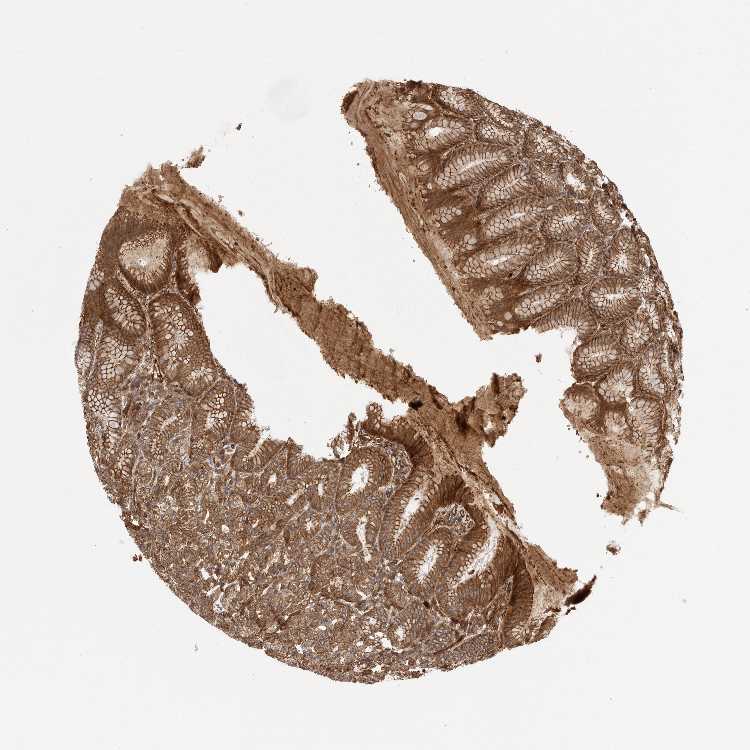

TISSUE PRIMARY DATA STOMACH Show tissue menu

STOMACH 1 - Antibody stainingi

Antibody staining in the annotated cell types in the current human tissue is reported as not detected, low, medium, or high, based on conventional immunohistochemistry profiling in selected tissues. This score is based on the combination of the staining intensity and fraction of stained cells.

Each image is clickable and will lead to virtual microscopy that enables deeper exploration of all samples and also displays staining intensity scores, fraction scores and subcellular localization as well as patient and tissue information for each sample.

Antibody HPA026846Antibody CAB016135

Glandular cells HighMedium